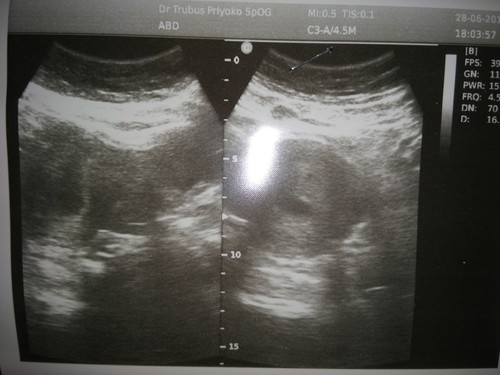

Halo bunda, aku baru bgt usg? Usia kandungan yang seharusnya 7minggu, setelah usg dokter bilang belum terlihat janin dan keadaan sangat lemah? kemungkinan kandunganku BO, tapi dokter minta buat balik lagi bulan depan dan lihat perubahan nya? Bun aku mau tanya solusi penambah vitamin supaya janinku nampak, kuat dan berkembang apa ya yang bagus? Aku mau tambahin vitamin selain dari dokter tadi

Baca lagiAku pun juga dinyatakan bo, sy dikasih obat penguat dan tiap minggu usg. Dan dr mau puasa smp sehari sblm takbiran itu sy flek terus walaupun hny sedikit tp tiap hari ad aja flek di celana. Seminggu sblm lebaran sy cek, dgn asumsi jika memang sy bo, keesokannya sy mau ambil rujukan untuk kuret. Qadarullah, pd saat sy cek janin ada bagus kantong jantungnya goyang dokter make sure bhwa smua insha alloh baik baik saja. Setlah mudik sy kontrol lg itu usia 9w, sy usg lagi dan alhamdulillah hasilnya baik janinnya sesuai dengan perkembangannya. Dan dokter memutuskan kontrol tiap bulan bukan seminggu sekali. Btw sy usg transvaginal, bukan usg perut krn klo uag perut di usia hamil muda kurang akurat. Obat penguat sy dksh resep buat jaga jaga tinggal tebus tp sy blm tebus smp skg. Sy dkah vit folamil genio dan juga calcium.... Insha alloh smua baik bajk saja. Dan ini dokter kedua yg menangani sy, sy cari dua pendapat.

bun, saya juga gitu, dari dokter katanya seharusnya usia kandungan 7minggu tapi hari hasil cek transvaginal pun, hasilnya belum ada detak jantung baby, dan di minta balik lagi sekitar 2 minggu lagi. saya tetap konsumsi asam folat dan obat penguat janin dari dokter. dan saya kembali ke dokter lain, sekitar 4 hari berikutnya, sudah ada detak baby. Dokter itu hitung dari HPHT kita, tapi kadang jadwal haid kita yang ga tepat bisa mempengaruhi usia kandungan juga. jadi keep calm aja bun, jangan asal konsumsi vitamin ya. karena dari dokter pasti sudah kasi vitamin dan obat penguat janin sesuai takarannya. dibawa happy dan ada harapan aja ya bun. semoga dedeknya sehat selalu

aq awal kmren pas usg 7 week jg blm kliatan bun baru kntongnya aja, cma kta spog itu wajar aja, minum aja vitamin yg d ksih spog sma kmren aq dsranin minum susu bumil 3x sehari, minum susu biasa (UHT) 2 gelas besar, banyak makan sayur, minum jus buah murni tnpa cmpuran gula/skm terus sma makan telur rebus 2 - 3 biji sehari, minum air putih sehari minimal 2 liter, memang bikin enek bun, tpi demi calon debaynya :) n kntrol 10 hari berikutnya Alhmdulillh udah ada jninnya bun, n harus fikir positif ya bun, semoga membantu bun

dulu juga aku gitu pas usg pertama kali bun, UK 7 mggu juga. cuma kelihatan kantung, terus lemah, mana pendaharan lagi. suruh balik 2 minggu kemudian buat di cek, soalnya takut BO. dikasih penguat kandungan, namanya premaston kalau gak salah. alhamdulillah UK 9 mnggu usg lagi udh kelihatan adeknya. Kalau BO biasanya ada gejalanya bund, silakan konsultasi lagi atau pindah dokter spog lain.